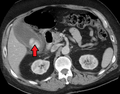

![]() Acute cholecystitis as seen on CT. Note the fat stranding around the enlarged gallbladder. | |

Right upper quadrant abdominal ultrasound is most commonly used to diagnose cholecystitis.[1][22][23] Ultrasound findings suggestive of acute cholecystitis include gallstones, fluid surrounding the gallbladder, gallbladder wall thickening, dilation of the bile duct, and sonographic Murphy's sign.[2] Given its higher sensitivity, hepatic iminodiacetic acid (HIDA) scan can be used if ultrasound is not diagnostic.[2][13] CT scan may also be used if complications such as perforation or gangrene are suspected.[13]